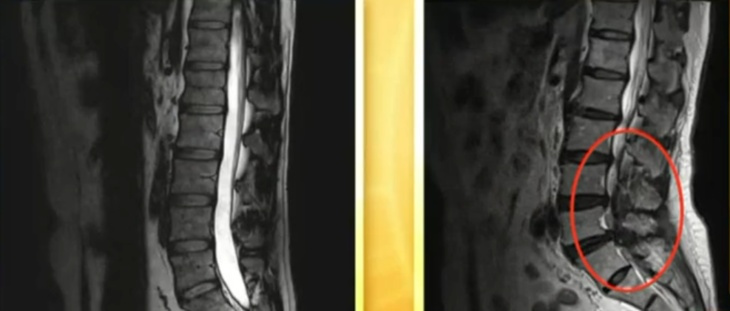

王先生在广告公司上班

总是长时间伏案工作

坐姿不正确,腰椎受力变形

结果患上了间歇性腰痛

后来用了这款腰间盘膏

每次疼的时候抹上一点

疼痛感立刻就能减轻

而且腰痛的次数也慢慢减少了